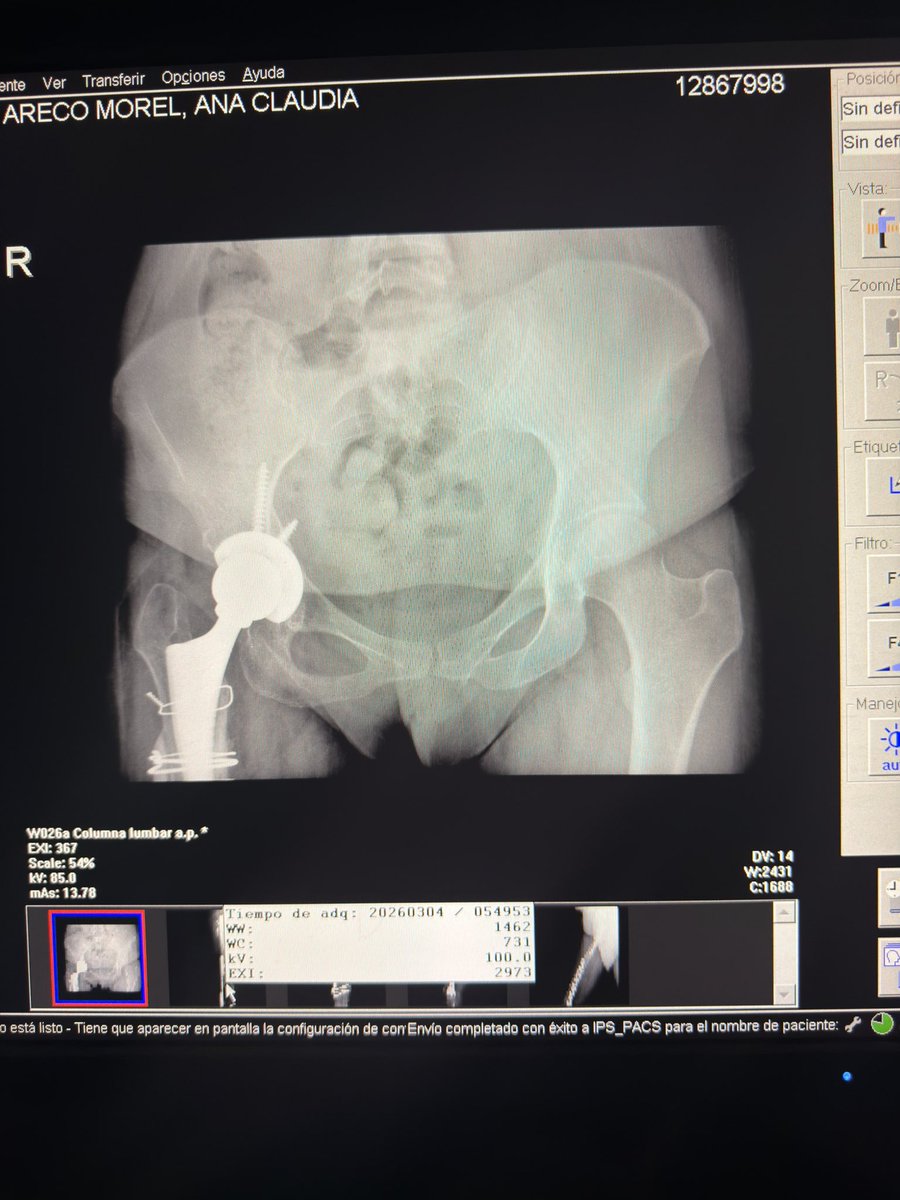

Essas sao as minhas radiografias, da pra ver o meu nome. Como o joelho nao esta dobrando (ja foram 5 cirurgias) eu nao consigo dirigir e ir com frequência nos correios e por isso uma menina se dispôs a fazer uma CEG de todas as minhas coisas ✨🩵 Estarei passando o contato dela.